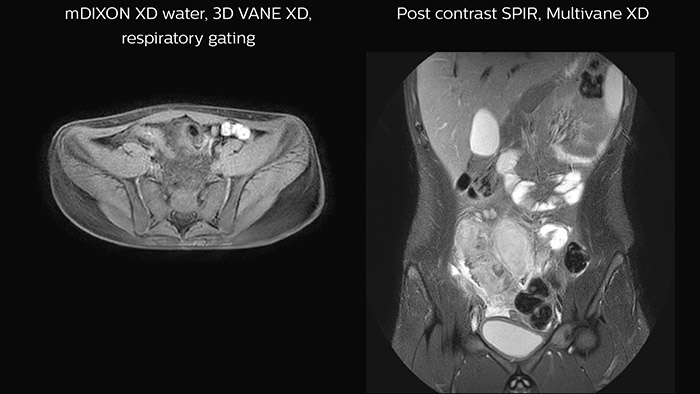

Crohn’s disease in the terminal ileum

A large abscess is visible near the terminal ileum, in the middle of the coronal image.

• Using latest techniques such as 3D VANE XD for free-breathing abdominal imaging, MultiVane XD for motion-free imaging in short scan time, mDIXON for excellent fat-free imaging.

The Ingenia Ambition gave Altona Children’s Hospital access to various novel scan techniques that are useful for pediatric imaging. “These modern technologies help us to scan anatomies where we saw challenges in the past, such as in the abdomen and thorax. With Ambition, we can perform high quality abdominal scans. As a result, the number of abdominal scans has increased substantially compared to our practice with our old system,” says Dr. Junge.

Features that provide remarkable benefits to Dr. Junge include Compressed SENSE, which allows to elevate spatial resolution, signal and scan time. MultiVane XD and 3D VANE XD employ radial k-space sampling and help to mitigate motion artifacts and improve robustness for different contrasts and for all age groups. The mDIXON FFE and mDIXON TSE methods nicely address challenges in fat-free imaging and provide multiple contrast types from one single scan. The achievable large field of view (FOV), high resolution and flexible echo times are certainly a huge benefit in examining children.